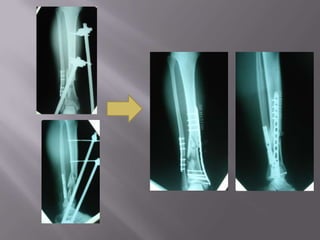

Obesidad(relativa)Fractura de PiernaMétodo de fijación:Tutor externo.

Placa y tornillos.

Clavo endomedular: (goldstandar)